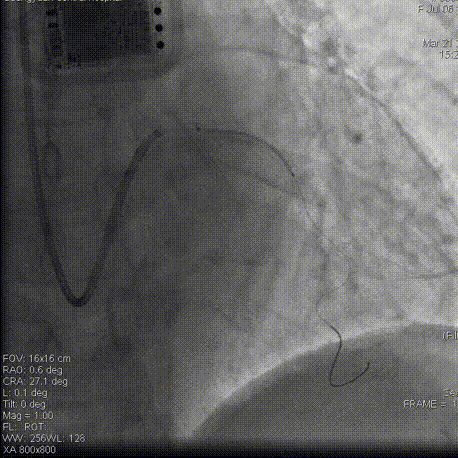

术毕影像

Gaia2通过闭塞段,交换为工作导丝,因左冠前降支扭曲,支架难以通过,在Telescope™ 导引延长导管支持之下顺利释放2枚支架